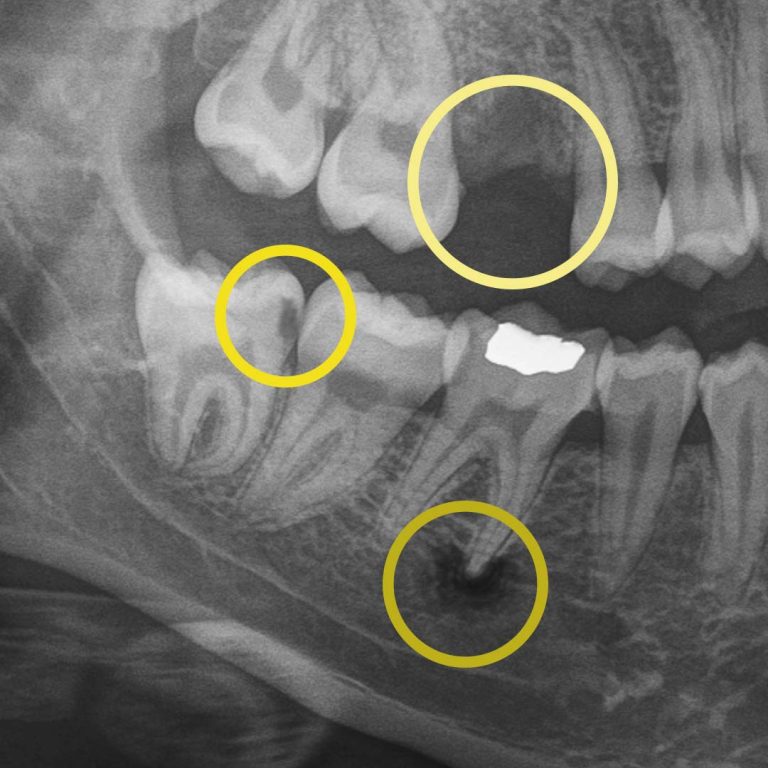

Digital X-rays allow us to see what the human eye simply can’t. They can detect hard and soft tissue changes, and if your dentist uses AI-technology, it can detect changes up to 10x quicker than traditional digital X-rays. More importantly, they help us personalize your care, track your oral health over time, and show you exactly what’s happening, so surprises are limited.

Digital X-rays allow us to look beyond what’s visible. They help us detect:

• cavities between teeth.

• early decay hiding under fillings or crowns.

• bone changes related to gum disease.

• infections at the root of a tooth.

• subtle cracks.

• wear patterns.

• missing primary teeth in children.

For example, during a routine digital X-ray, we may notice a small shadow between two teeth. To the naked eye, everything can look healthy, but that faint shadow often tells us the enamel in that area is starting to weaken. This is considered early-stage tooth decay, sometimes called early “caries.”

At your next X-ray visit, we’ll compare images to see whether that spot has stabilized or improved. If the area worsens and the enamel breaks down further, a small dental filling may be necessary to prevent deeper decay damaging the tooth structure. If the decay continues unchecked and reaches the inner portion of the tooth where the nerve lives, treatment becomes more complex, often requiring root canal therapy, which can be time-consuming, uncomfortable, and costly.

While catching early tooth decay is one of the most common reasons we rely on digital X-rays, it’s far from the only one. Dental imaging also helps us monitor bone levels to detect gum disease before it leads to tooth loss, identify disease that can’t be seen during an exam, and track hard and soft tissue changes caused by grinding, acid wear, or dietary habits. A complete set of digital X-rays is necessary every few years to ensure the health of all your teeth. This allows you to keep your natural teeth longer.